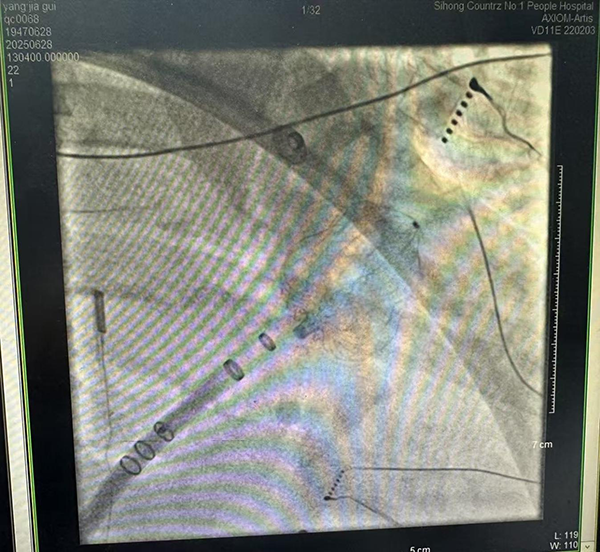

黃淮網(wǎng)(王銀)6月28日,泗洪縣第一人民醫(yī)院(徐州醫(yī)科大學(xué)附屬醫(yī)院泗洪分院)心血管內(nèi)科等多學(xué)科團(tuán)隊(duì)在徐州醫(yī)科大學(xué)附屬醫(yī)院李承宗主任指導(dǎo)下,開(kāi)展全縣首例“心房顫動(dòng)射頻消融術(shù)+左心耳封堵術(shù)”一站式手術(shù)。該手術(shù)通過(guò)微創(chuàng)介入技術(shù),同步解決患者房顫心律問(wèn)題及卒中風(fēng)險(xiǎn)。7月2日,患者順利康復(fù)出院。這標(biāo)志著徐醫(yī)附院泗洪分院在心律失常治療領(lǐng)域邁入精準(zhǔn)化、綜合化的新階段,進(jìn)一步擦亮了徐醫(yī)附院“院府合作”的“泗洪品牌”。

患者楊大爺(化名)罹患房顫多年,長(zhǎng)期飽受心悸、心衰與卒中威脅,50天前因心源性腦梗死導(dǎo)致右側(cè)肢體肌力下降到泗洪分院就診,經(jīng)過(guò)積極抗凝及改善心功能治療,并在徐醫(yī)附院專(zhuān)家指導(dǎo)下聯(lián)合制定治療方案,心血管內(nèi)科、麻醉科、超聲科、影像科等多學(xué)科團(tuán)隊(duì)深入討論,排除手術(shù)禁忌證,認(rèn)真制定手術(shù)方案及應(yīng)急預(yù)案,并與患者家屬充分溝通后,于6月28日在全身麻醉下,成功實(shí)施了在心腔內(nèi)超聲導(dǎo)管(ICE)引導(dǎo)下的“一站式”手術(shù),歷時(shí)4.5小時(shí)。

傳統(tǒng)治療中,房顫患者需分階段解決心律失常和血栓預(yù)防問(wèn)題。此次開(kāi)展的“一站式”手術(shù)創(chuàng)新性融合兩項(xiàng)關(guān)鍵技術(shù):1.射頻消融術(shù):通過(guò)導(dǎo)管精準(zhǔn)阻斷異常電信號(hào),恢復(fù)正常心律;2.左心耳封堵術(shù):封堵房顫患者血栓最易形成的左心耳,顯著降低卒中風(fēng)險(xiǎn)達(dá)90%以上。手術(shù)僅需股靜脈穿刺,創(chuàng)傷小、恢復(fù)快,為高齡、高卒中風(fēng)險(xiǎn)患者提供了更安全有效的治療選擇。